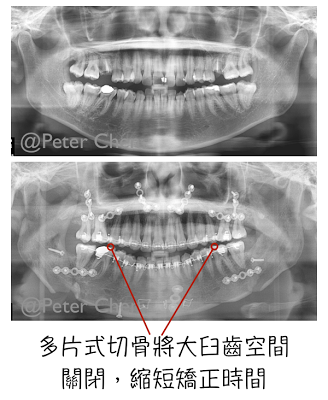

我告訴她牙齒排列的部分需要和矯正醫師討論,如果適合,是可以利用多片式切骨手術 ( Multi-segmental Osteotomy ) 將上排缺牙空間利用手術關閉,縮短矯正時間。

後來利用牙模及模擬與矯正醫師潘醫師確認,可以用上顎多片式切骨手術 ( LeFort I 2 pieces osteotomy ) 一方面將上排牙齒缺牙空間關閉,一方面將上顎後退,再將下顎前移,並合併下巴手術,